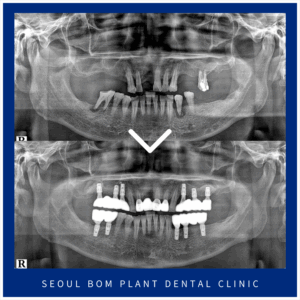

방이역치과 임플란트 식립시 개인의 구강상태를 하나하나 고려하고

방이역치과 임플란트 식립시 개인의 구강상태를 하나하나 고려하고 안녕하세요. 서울봄플란트치과 대표원장 송원섭입니다.^^ 치아는 우리 신체 부위에서 단단한 부위 중 하나인데요. 하지만 음식물을 씹고 잘게 부수는 저작기능을 하다 보니 쉽게 마모되고,…